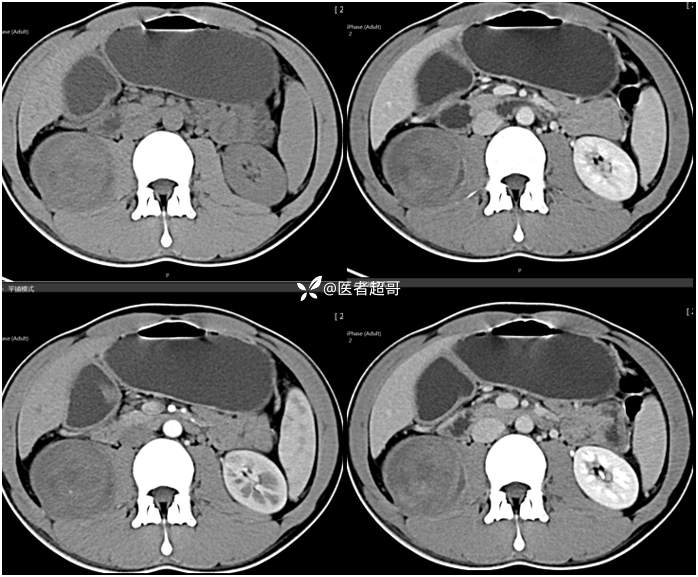

【影诊笔记754】腰痛就诊,腹膜后实性占位,请诊断分析!

主 诉:腰痛2月。

现病史:患者2月前无明显诱因出现腰背部疼痛,夜间为著。患者无头痛、头晕,无恶心、呕吐,无胸闷、憋气,无腹痛、腹胀。无尿频、尿急、尿痛等现象。患者在院外未作特殊治疗。为求进一步诊疗,来我院肾内科门诊就诊。门诊行双肾、输尿管、膀胱(前列腺)彩超提示:腹膜后实性占位。患者遂来我科就诊。我科以“腰痛”收治入院,患者自发病以来,神志清,精神可,饮食可,睡眠差。小便如上述,大便未见明显异常。体重无明显增减。